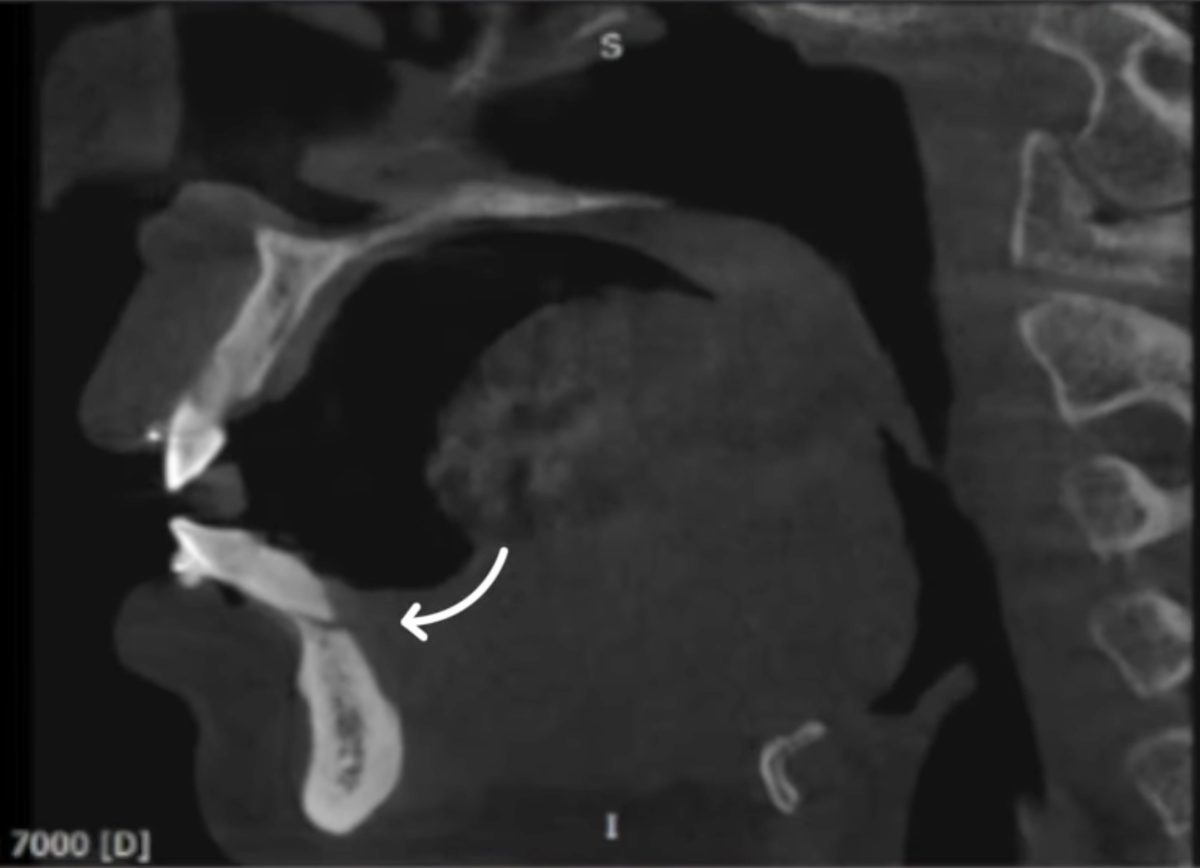

Теперь посмотрим на данные компьютерной томографии.

Что мы видим:

• полное отсутствие костной ткани вокруг части корня

• небольшую резорбцию верхушки корня

• корень практически полностью вышел за пределы костной ткани

• частичную утрату связочного аппарата

• рецессию десны

То есть перед нами классический пример выхода корня зуба за пределы кортикальной пластинки.